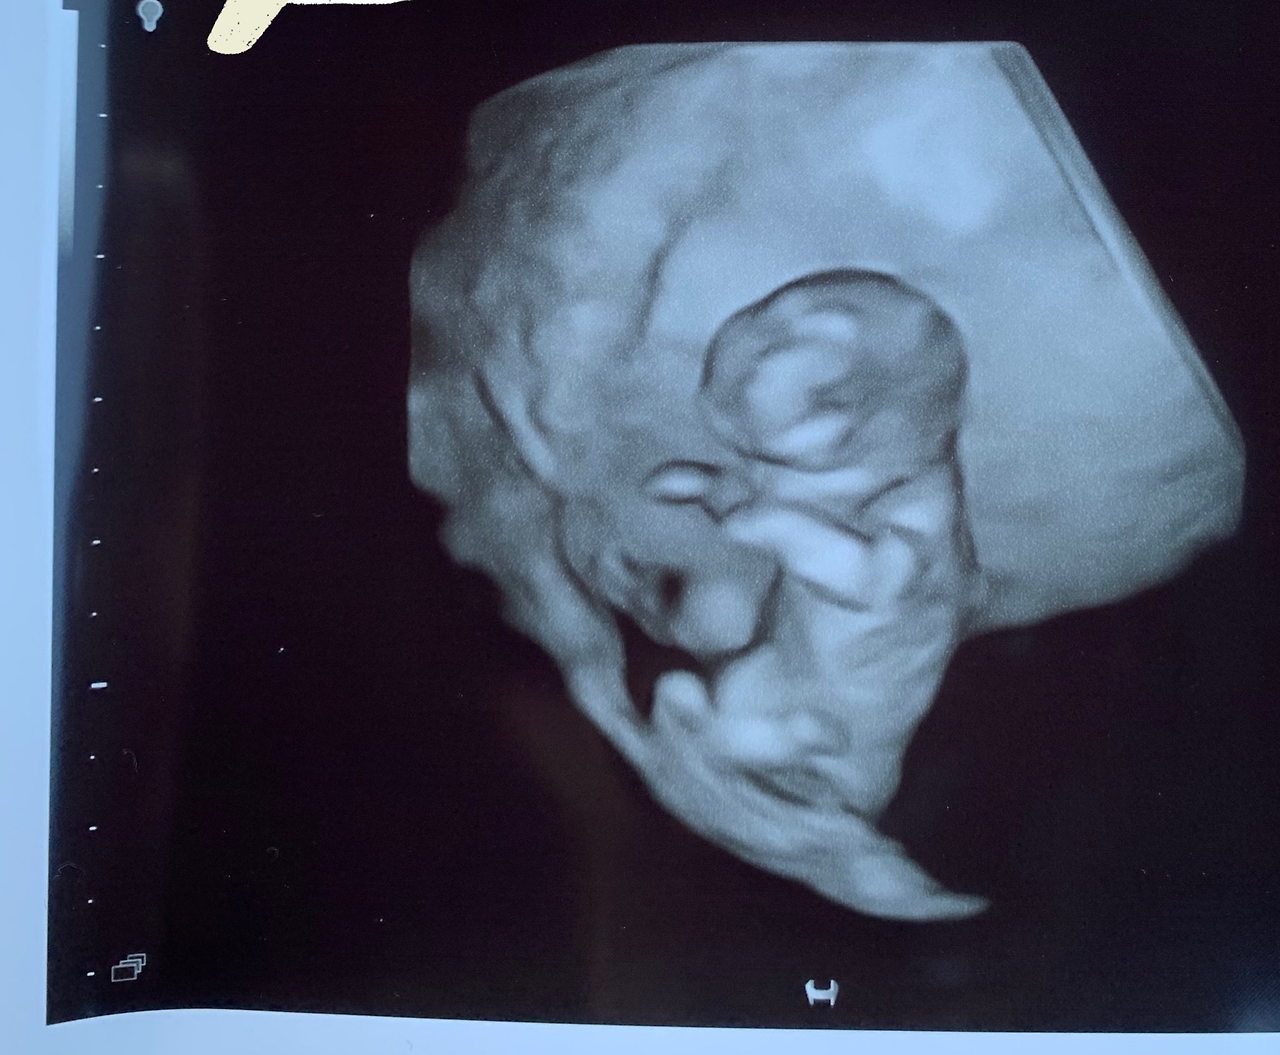

임신 12주차였다. 꽤나 초기에 속한다. 임신 사실을 처음 알게 된 뒤 한 달 반 남짓 된 시점. 어느 정도 안정권에 접어들었다고 스스로 안심시키고 싶긴 해도 성별을 알 수 있는 시기는 대개 16주차쯤으로 일컬어진다. 물론 개인차도 존재하고 차후 성별 반전이 있을 수도 있겠으나 그 시기쯤 초음파를 보면 대부분 아기의 성별을 알 수 있다고들 했다. 미국 산부인과 두 번째 방문 뒤 NIPT 니프트 검사로 일컬어지는유전자 검사 한 종류를 받게 됐다. 임신 고위험군은 아니었으나 보험 커버가 된다면 아기가 건강한지 미리 확인차 받는 것도 좋겠다는 주변 지인의 추천을 받아 시행한 검사. 혈액 채취를 통해 진행된 유전자 검사라 결과지를 수령하면 자연스레 아기 성별도 알 수 있었다. (한국에서는 니프트 검사를 받더라도 성별 고지를 해주지 않는다는 이야기를 들었다.) 이메일을 기다리라고 결과지 보내주겠다는 이야기를 듣긴 했는데 젠더가 그렇게나 궁금했다. Girl or Boy?

우리 아기가 미키마우스임을 알아챘던 임신 12주차 가을날